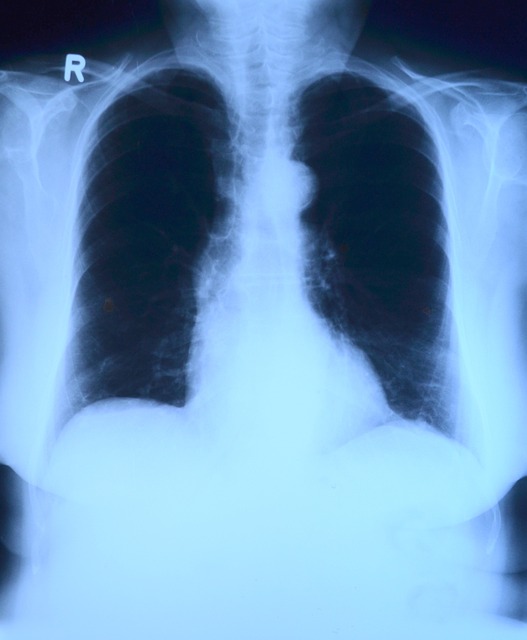

์์ธํฌ์ฑ ํ์๊ณผ์ ์ฐจ์ด์ ์?

ํ์์ ํฌ๊ฒ ๋ ๊ฐ์ง๋ก ๋ถ๋ฅ๋ฉ๋๋ค: **๋น์์ธํฌ์ฑ ํ์(NSCLC)**๊ณผ **์์ธํฌ์ฑ ํ์(SCLC)**์ ๋๋ค. ์ด ๋ ๊ฐ์ง๋ ์กฐ์งํ์ ํํ๋ฟ ์๋๋ผ, ์งํ ์๋, ์น๋ฃ ๋ฐ์, ์ํ ๋ฑ์์ ํฐ ์ฐจ์ด๋ฅผ ๋ณด์ ๋๋ค.

| ๊ตฌ๋ถ | ๋น์์ธํฌ์ฑ ํ์(NSCLC) | ์์ธํฌ์ฑ ํ์(SCLC) |

| ๋ฐ์ ๋น์จ | ์ ์ฒด ํ์์ ์ฝ 85% | ์ ์ฒด ํ์์ ์ฝ 15% |

| ์งํ ์๋ | ๋๋ฆฐ ํธ, ๋จ๊ณ๋ณ ์งํ | ๋งค์ฐ ๋น ๋ฅด๊ฒ ์งํ ๋ฐ ์ ์ด |

| ์น๋ฃ ๋ฐฉ๋ฒ | ์์ , ํญ์, ๋ฐฉ์ฌ์ , ํ์ ·๋ฉด์ญ์น๋ฃ | ํญ์+๋ฐฉ์ฌ์ ์ค์ฌ, ์์ ์ ๊ฑฐ์ ์์ |

| ์ฌ๋ฐ๋ฅ | ๋ณ๊ธฐ์ ๋ฐ๋ผ ๋ค๋ฆ | ๋์ (6๊ฐ์~1๋ ๋ด ์ฌ๋ฐ ๋ง์) |

| ์ํ (5๋ ์์กด์จ) | 10~60% (๋ณ๊ธฐ๋ณ ์ฐจ์ด ํผ) | 10% ๋ฏธ๋ง |

1. ์งํ ์๋

์์ธํฌ์ฑ ํ์์ ์งํ์ด ๋งค์ฐ ๋น ๋ฅด๋ฉฐ, ์ง๋จ ๋น์ ์ด๋ฏธ ์ ์ด๊ฐ ๋์ด ์๋ ๊ฒฝ์ฐ๊ฐ ๋ง์ต๋๋ค. ๋ฐ๋ฉด, ๋น์์ธํฌ์ฑ ํ์์ ์๋์ ์ผ๋ก ์ฒ์ฒํ ์๋ผ๊ณ ์ด๊ธฐ ๋ฐ๊ฒฌ ์ ์์ ์ ์น๋ฃ๊ฐ ๊ฐ๋ฅํ ์ ์์ต๋๋ค.

2. ์น๋ฃ ๋ฐฉ๋ฒ

์์ธํฌ์ฑ ํ์์ ๋น ๋ฅด๊ฒ ์๋ผ์ง๋ง ํญ์์ ๋ ๋ฐฉ์ฌ์ ์น๋ฃ์ ์ ๋ฐ์ํฉ๋๋ค. ๊ทธ๋ฌ๋ ์ฌ๋ฐ์ด ์ฆ๊ณ ์์กด์จ์ด ๋ฎ์ต๋๋ค. ๋น์์ธํฌ์ฑ ํ์์ ์์ ์ด ๊ฐ๋ฅํ๊ณ , ์ต๊ทผ์๋ ๋ฉด์ญํญ์์ ์ ํ์ ํญ์์ ์ ํจ๊ณผ๊ฐ ์

์ฆ๋๋ฉด์ ์น๋ฃ ์ ํ์ง๊ฐ ๋์ด์ก์ต๋๋ค.

3. ์ํ

์ผ๋ฐ์ ์ผ๋ก ์์ธํฌ์ฑ ํ์์ ์ํ๊ฐ ๋์ ์์ผ๋ก ๋ถ๋ฅ๋๋ฉฐ, ์ง๋จ ํ 2๋

์์กด์จ์ด 10% ๋ฏธ๋ง์

๋๋ค. ๋ฐ๋ฉด, ๋น์์ธํฌ์ฑ ํ์์ ๋ณ๊ธฐ๋ณ ์์กด์จ ์ฐจ์ด๋ ํฌ์ง๋ง, ์กฐ๊ธฐ ๋ฐ๊ฒฌ ์ 5๋

์์กด์จ์ด 60% ์ด์์ผ๋ก ๋ณด๊ณ ๋ฉ๋๋ค.